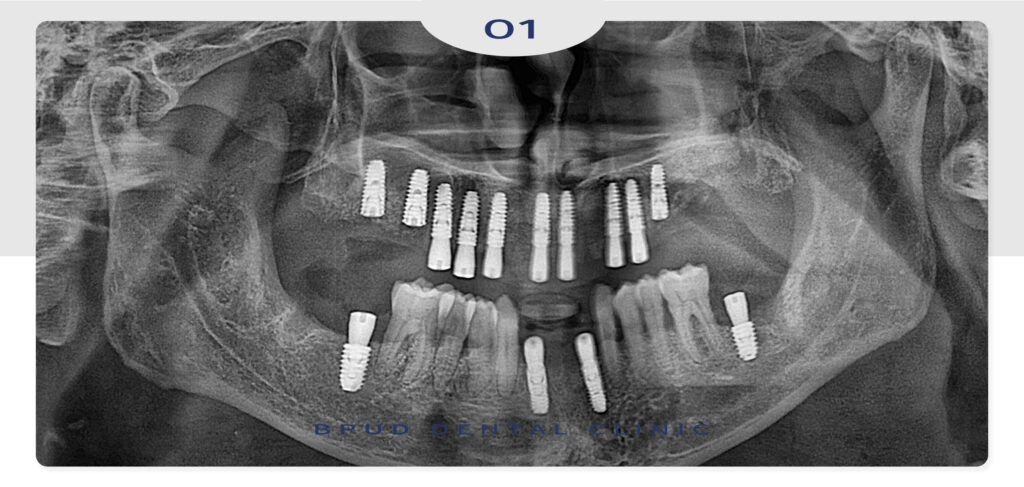

파노라마 촬영 시 동요도가 많이 보이는 치아들 모두

심한 치주염으로 인해 발치가 필요한 상황이었고

위쪽의 경우 상악동까지 골소실이 진행되어

양측 상악동 거상술을 동반한 뼈이식을 통해

치조골 재건 후 임플란트 식립을 진행하기로

계획을 수립하였습니다.